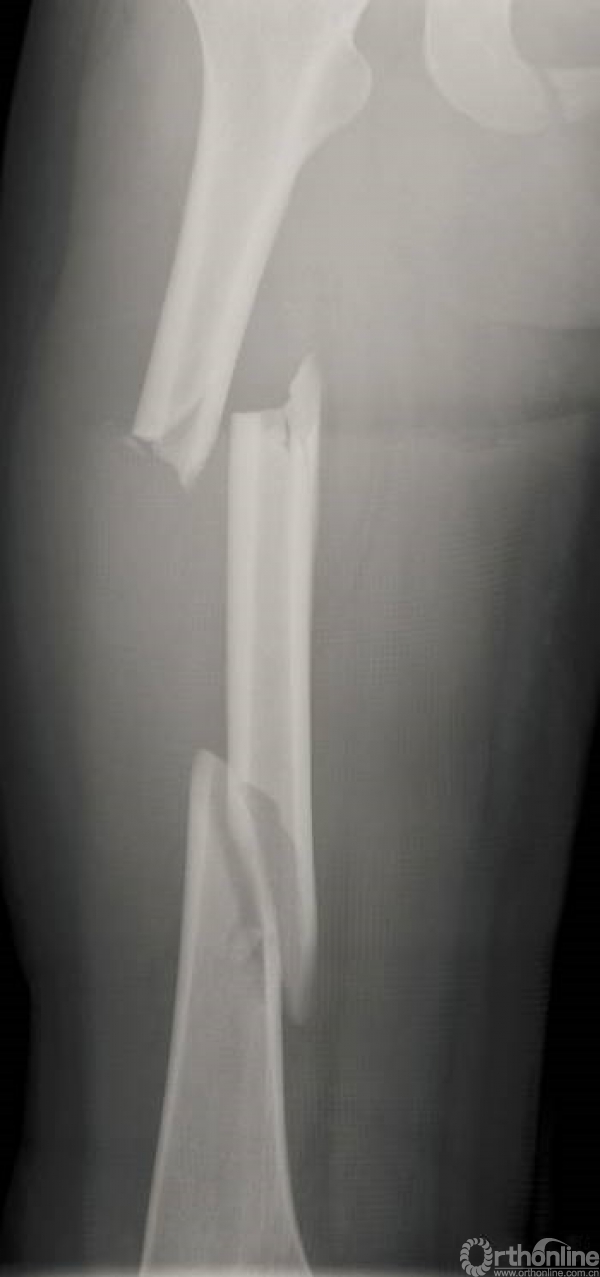

术后